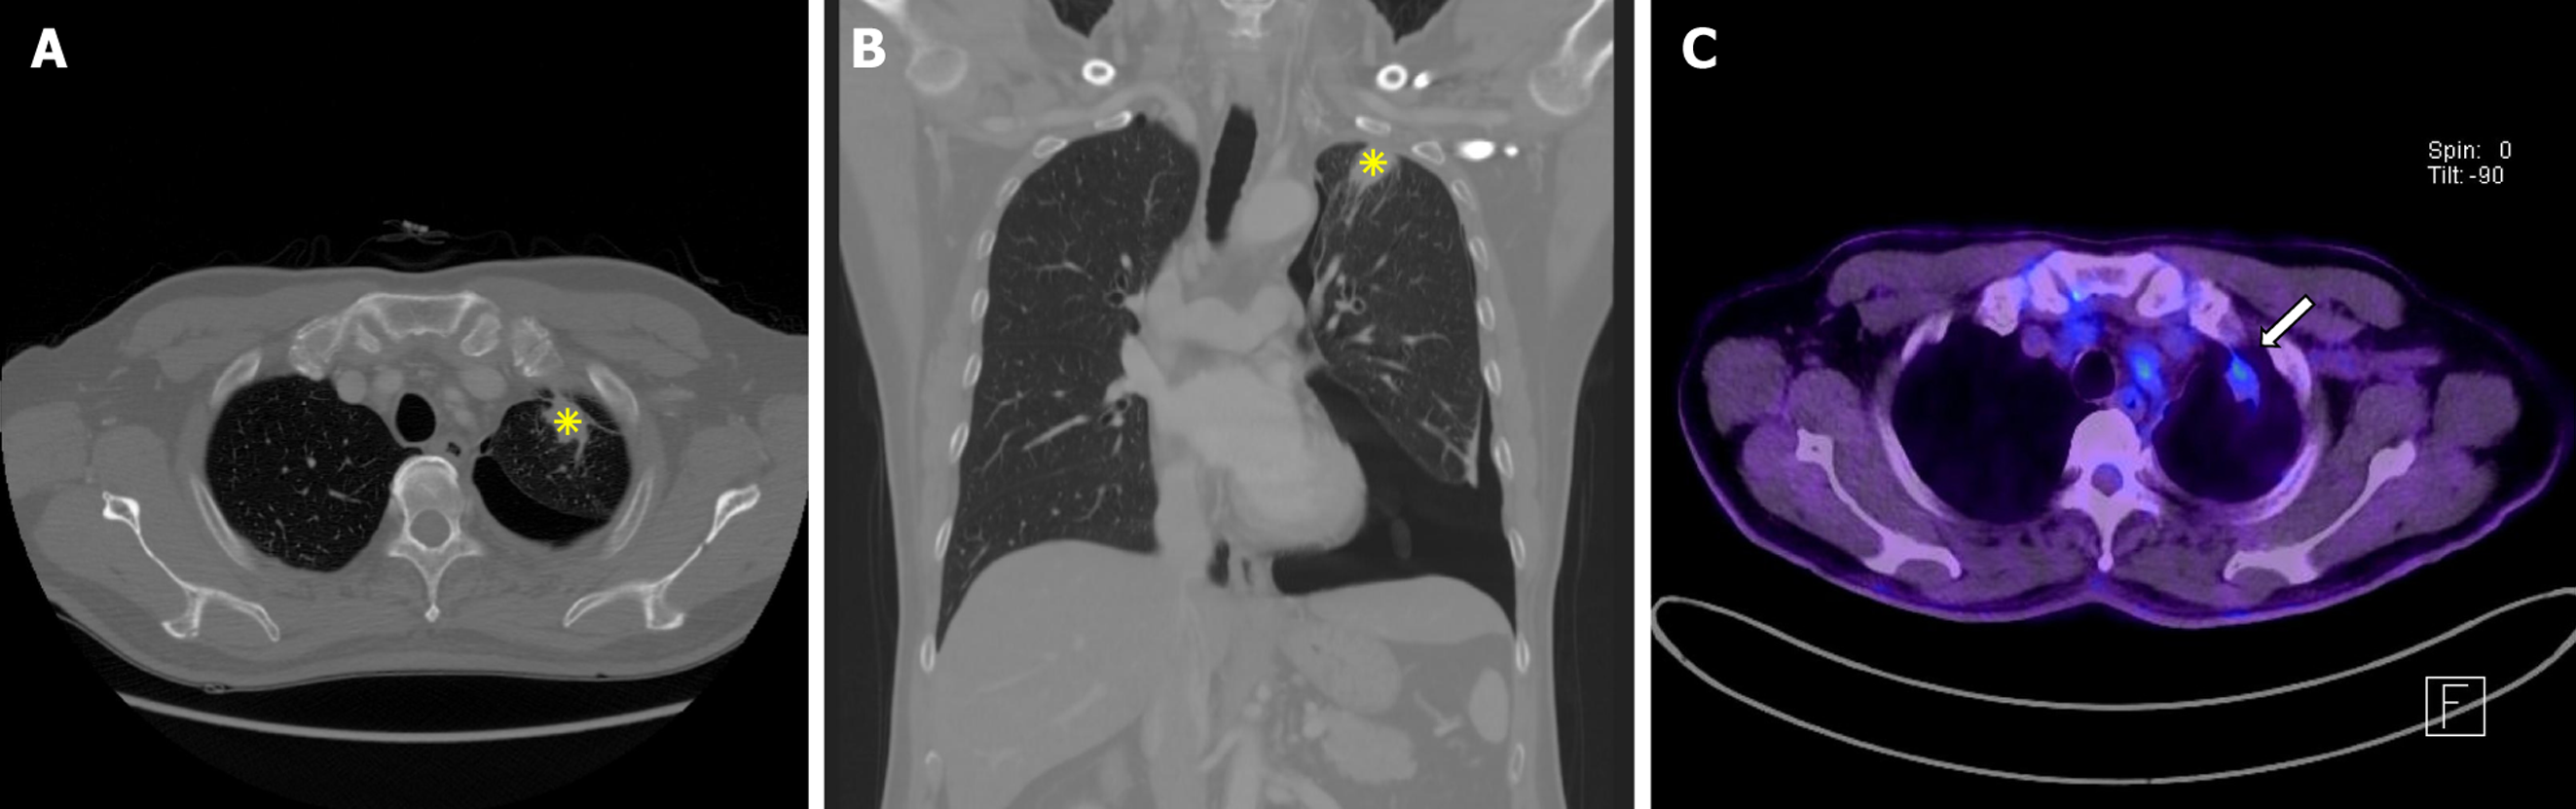

Figure 1 Imaging results.

A and B: Chest computed tomography demonstrated left upper lobe subpleural consolidation with pleural thickening and associated pneumothorax. Axial chest computed tomography showed subpleural consolidation (asterisks) and pleural thickening in the left upper lobe (A). Coronal chest computed tomography confirmed subpleural consolidation (asterisks) with adjacent pneumothorax (B); C: 18F-fluorodeoxyglucose positron emission tomography/computed tomography. Moderate fluorodeoxyglucose uptake (maximum standardized uptake value = 3.2) was observed in the left upper lobe (arrows), suggesting malignancy.